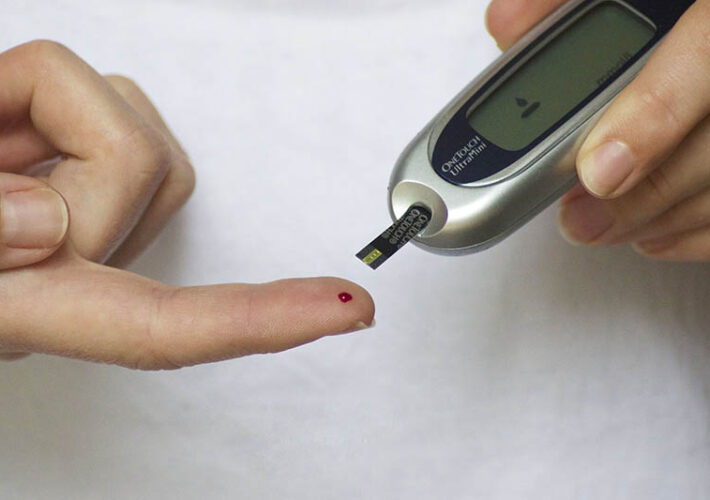

A couple weeks after my first midwife appointment I was booked in for a glucose test and 2nd appointment with my midwife due to having a higher BMI.…